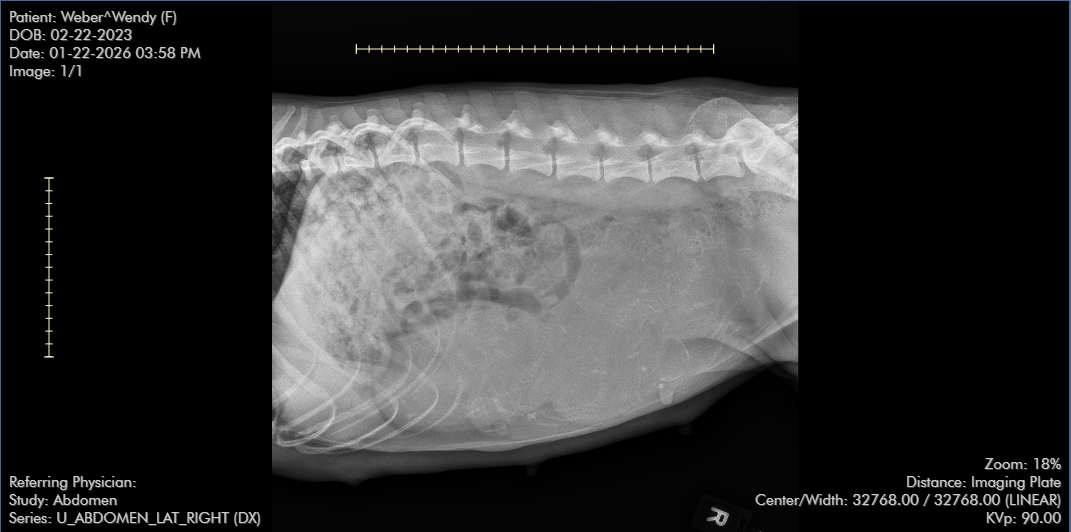

As promised, we headed to the vet on the 22nd for Wendy’s official puppy count X-ray. The results are in, and it’s going to be a full house! The vet confirmed there are at least 7 puppies tucked safely in her now very round, very pregnant tummy.

Now, here is where it gets interesting! I’ve spent some time further analyzing those X-ray images myself. While I’m certainly not a radiology tech, I’ve been looking at those tiny spines and skulls so closely I feel like I could see them in my sleep.

Looking at the way a few of those little ones are shadowed in the back, I swear I can see a few more hiding in there! Could we be looking at 8? 9? Only time (and Wendy!) will tell. It’s always such a thrill to see if the final count matches the X-ray, or if Wendy has a few extra surprises up her sleeve for delivery day.

How many puppies do you see?